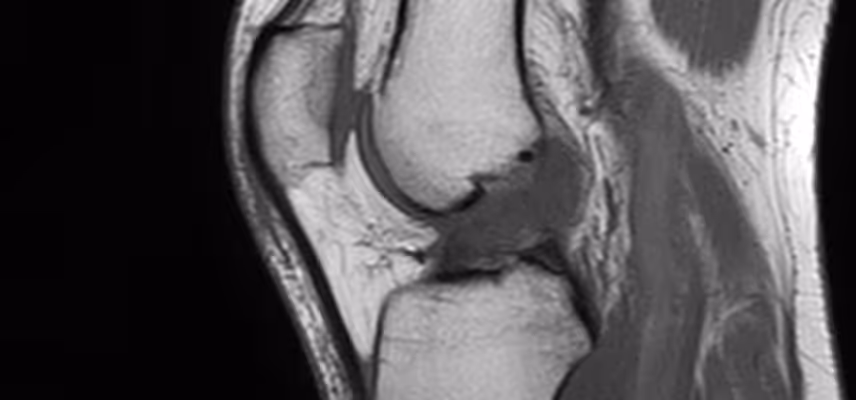

- ✅ Skręcenia lub niestabilności w kolanie (ACL, uszkodzonie łąkotki, uszkodzenie więzadeł MCL, LCL)

- ✅ Stanu po artroskopii kolana (np. szyciu łąkotki, meniscektomii łąkotki, rekonstrukcji więzadła ACL, osteotomii)

Nie, skierowanie nie jest wymagane. Jeśli posiadasz jakąkolwiek dokumentację medyczną (USG, RTG, rezonans magnetyczny, wypis ze szpitala), zabierz ją ze sobą – będzie ona bardzo pomocna w planowaniu terapii.